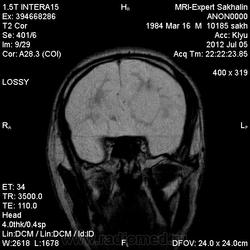

1 случай -локальная гемиатрофия.2 случай-диффузная.

Молодой человек после автомобильной аварии.3 года лежит.Двигаются только глаза.Зрелище душещипательное.

Евгений, конечно же, мои случаи не являются "чистой" атрофией-согласна.Мне пока не встречались случаи болезни Пика, Альцгеймера и другие "чистой воды" атрофии.Второй случай- состояние после длительной комы вследствие автодорожной травмы 3 года назад.Пациент проходил исследование в прошлом году , в этом родители привезли на динамику.